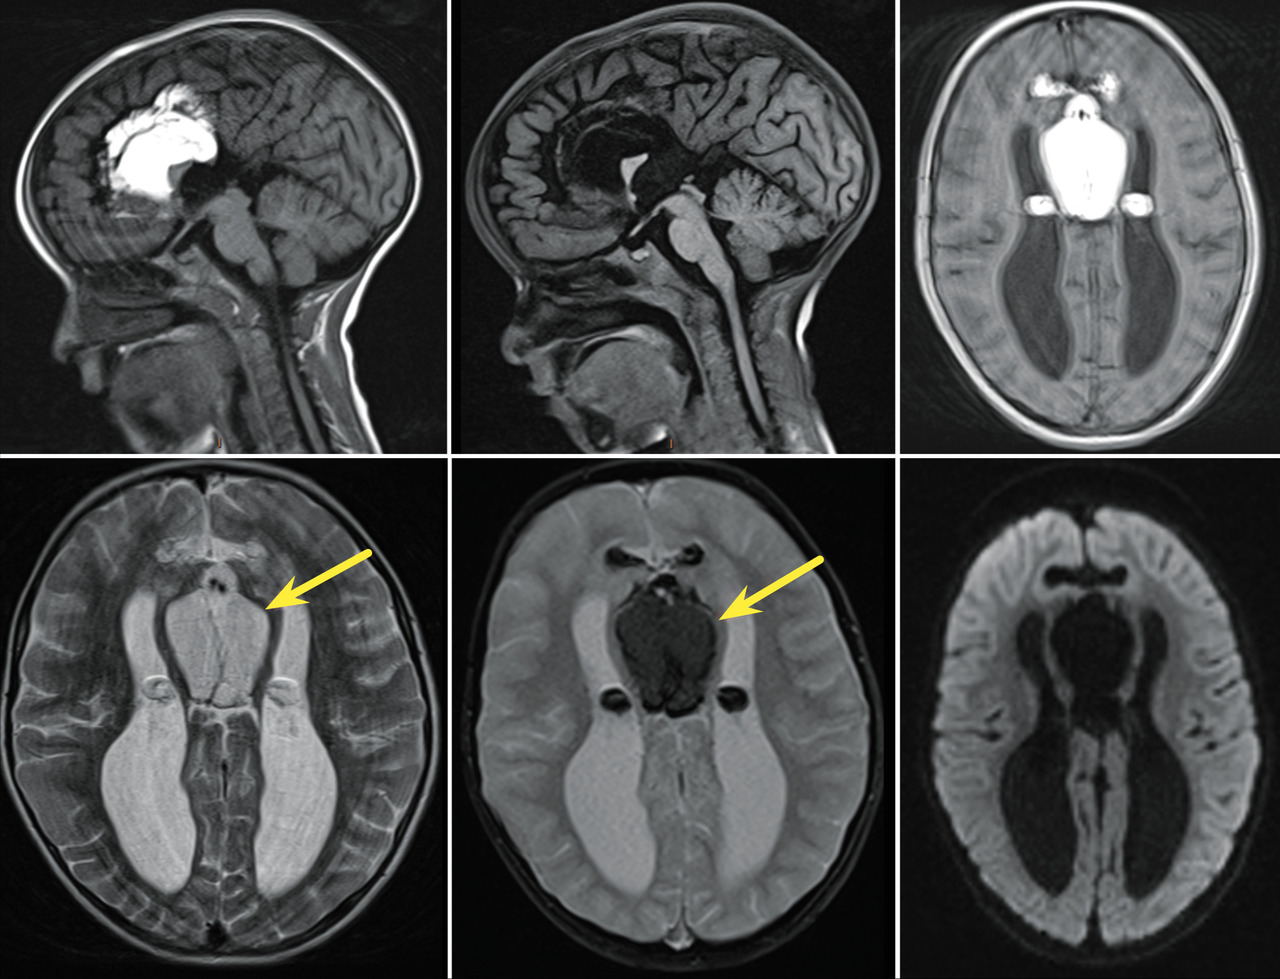

Un enfant âgé de 4 ans, sans antécédents pathologiques notables, est vu en consultation pour des crises épileptiques évoluant depuis un mois. L’examen clinique retrouve un patient conscient, stable sur le plan hémodynamique, normotendu, normocarde, et le bilan biologique est sans anomalie. Un électroencéphalogramme est réalisé, révélant une activité épileptiforme bilatéralement synchrone et généralisée. Le patient est mis sous traitement antiépileptique avec une amélioration clinique. Une imagerie par résonance magnétique (IRM) cérébrale effectuée dans le cadre du bilan étiologique montre une formation au niveau de la ligne médiane interhémisphérique, avec absence de visualisation du corps calleux en hypersignal T1, s’effaçant sur la séquence T1FS, en hypersignal intermédiaire T2, sans restriction de la diffusion, renfermant des calcifications linéaires et périphériques sur la séquence T2*, étendues latéralement aux espaces sous-arachnoïdiens antérieurs et au plexus choroïde (figure). Cette imagerie permet de poser le diagnostic de lipome du corps calleux.

Les lipomes intracrâniens sont des lésions congénitales malformatives très rares  ; l’extension dans le ventricule latéral est encore plus rare.1 Ils sont considérés comme des hétérotopies plutôt que comme des tumeurs.2 Ils sont localisés principalement dans la région péricalleuse.2 Les lipomes intracrâniens sont morphologiquement classés en deux groupes  :1

• les lipomes antérieurs (tubulonodulaires), qui peuvent s’étendre dans les plexus choroïdes des ventricules latéraux  ;

• les lipomes postérieurs (curvilignes), qui siègent plus en arrière sur le splénium.

Ils sont associés dans plus de la moitié des cas à des malformations congénitales telles que l’agénésie ou la dysgénésie du corps calleux.1 La plupart des lipomes du corps calleux sont asymptomatiques et sont découverts fortuitement. Leur pronostic et les symptômes dépendent de la malformation associée.1